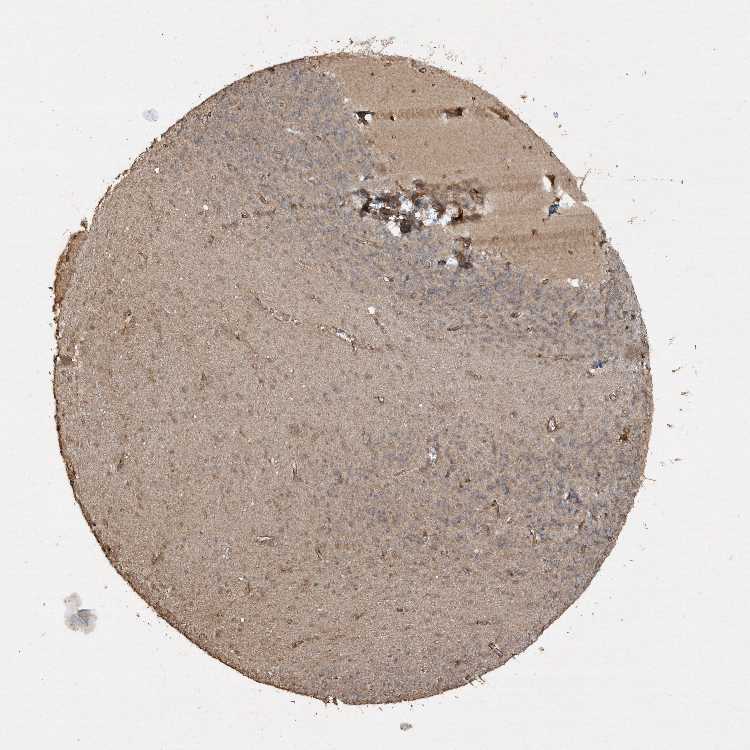

CEREBELLUM - Antibody stainingi

Antibody staining in the annotated cell types in the current human tissue is reported as not detected, low, medium, or high, based on conventional immunohistochemistry profiling in selected tissues. This score is based on the combination of the staining intensity and fraction of stained cells.

Each image is clickable and will lead to virtual microscopy that enables deeper exploration of all samples and also displays staining intensity scores, fraction scores and subcellular localization as well as patient and tissue information for each sample.

Antibody HPA037649

Purkinje cells Medium

Cells in granular layer Low

Cells in molecular layer Low